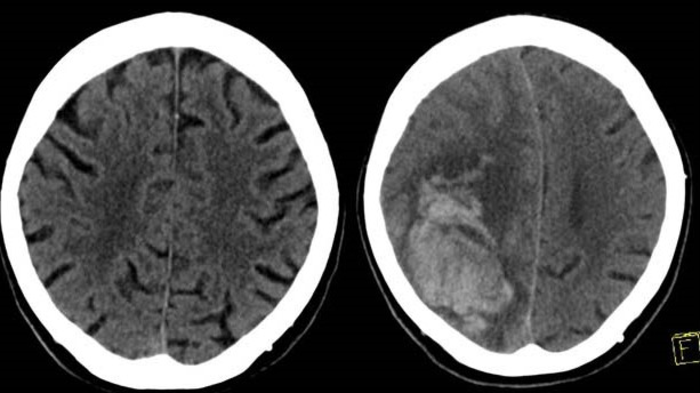

Intracranial hemorrhage occurs when blood vessels within the brain rupture, releasing blood into the brain tissue. In a delayed traumatic intracranial hemorrhage, bleeding in the brain occurs after the initial trauma, usually within 48 hours, after an initial negative head CT.

Adults taking blood thinners who suffer head trauma typically undergo CT imaging of the brain. However, the standard of care beyond initial imaging is not well defined. Some hospitals admit patients for observation and repeat CT imaging, while others may discharge a patient who does not have intracranial hemorrhage and is in stable condition.